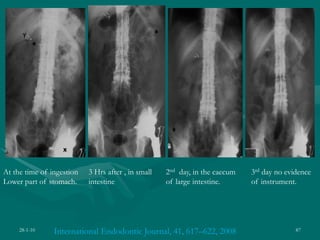

International Endodontic Journal, 41, 617–622, 2008

At the time of ingestion

Lower part of stomach.

3 Hrs after , in small

intestine

2nd day, in the caecum

of large intestine.

3rd day no evidence

of instrument.